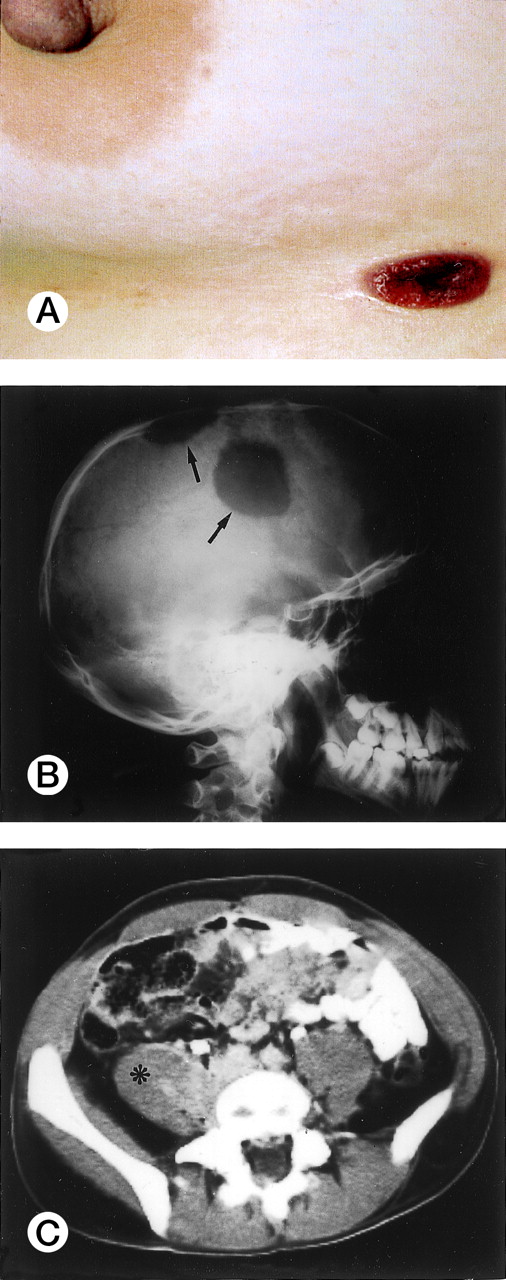

Clinical and laboratory findings were available in 78 of 96 cases (53 ALK+ and 25 ALK−) and are summarized in Table 2. ALK+ lymphoma frequently occurred in the first three decades of life (Fig 2; mean age, 22.01 ± 10.87 years; age range, 3 to 52 years). The present series included 12 pediatric patients and 41 adult patients (>16 years of age). The male/female (M/F) ratio was 3.0, with male predominance being particularly striking in the second to third decades of life (M/F ratio, 6.5; Fig 2). According to the Ann Arbor staging system, 28% of patients had stage I-II and 72% had stage III-IV disease. Most cases (75%) presented with systemic symptoms (high fever and/or weight loss in the absence of pruritus). Lymphadenopathy was present in 92% of patients; 40% had exclusively nodal disease. Extranodal involvement was frequent (60%), with 41% of patients showing two or more extranodal sites. Skin (usually nodules or ulcerated lesions; Fig3A), bone (Fig 3B), and soft tissues (Fig 3C) were the most frequently involved sites (skin, 21%; bone, 17%; soft tissues, 17%), followed by bone marrow (11%), lung (11%), and liver (8%). Tumor cells infiltrating the marrow ranged in size from small atypical cells to large anaplastic elements, and in one case involvement was only evident by ALK immmunostaining of the bone marrow biopsy (Fig 1F). Three of the 6 patients with bone marrow involvement had concomitant tumor cells circulating in the peripheral blood. None of the 6 cases with affected bone marrow showed concomitant skin lesions. The following extranodal sites were rarely involved: pleura (n = 3), central nervous system (CNS; n = 2), gut (n = 1), testis (n = 1), and parotid (n = 1).

Extranodal involvement in ALK+ lymphoma. (A) Umbelicated skin lesion in a 38-year-old women. (B) Large ostelytic lesions of the skull (arrows) in a 14-year-old boy. (C) Involvement of the right psoas muscle (asterix) in a 25-year-old man.